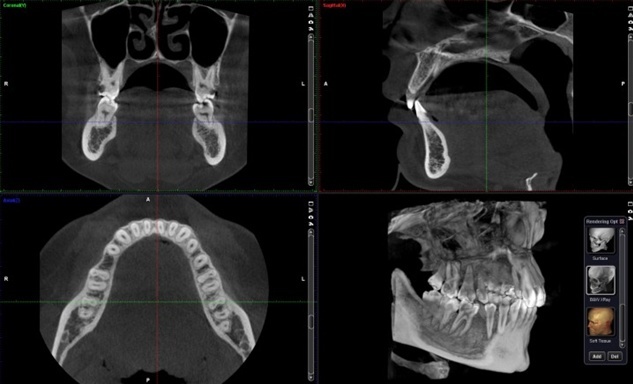

3D компьютерная томография

1. Перед началом лечения пациент проходит первоначальную диагностику,(КЛКТ + цифровые слепки).

Сканирование челюсти с помощью конусно-лучевой компьютерной томографии(КЛКТ) и сканера позволяет получить точную модель анатомии: объём костей, расположение нервов, корней и синусов. Это основа для расчётов и прогнозирования.

Результат: уменьшение хирургической травмы, снижение риска осложнений.